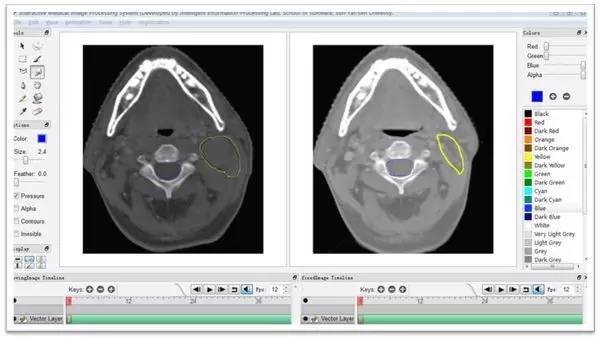

数据的标注是否专业?

医疗数据最大的痛点就在于如何进行大批量的标注,如何保证标注的质量。以医学影像为例,虽然前几年影像云平台的建立积累了大量数据,但基本都没有对病灶进行标注,而这个工作只能由专业医师来完成。做智能安防的公司以很低的成本雇些临时工就能完成对行人、车辆、路标的标注,这足够让智能医疗公司羡慕嫉妒恨了。医学专家临床和科研的负担都很重,没有时间给创业公司标注数据,即使花钱也很难请到,折中的办法就是找医学院的学生。你喂给机器什么样的数据,就决定了它能学出什么水准的结果,很难想象用医学院实习生标注的数据能学出专家的水平来。

医疗数据标注需要专业医生的配合